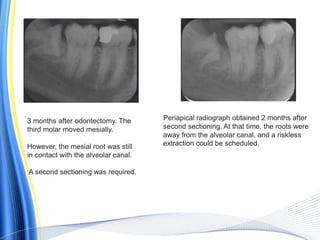

3 months after odontectomy. The

third molar moved mesially.

However, the mesial root was still

in contact with the alveolar canal.

A second sectioning was required.

Periapical radiograph obtained 2 months after

second sectioning. At that time, the roots were

away from the alveolar canal, and a riskless

extraction could be scheduled.